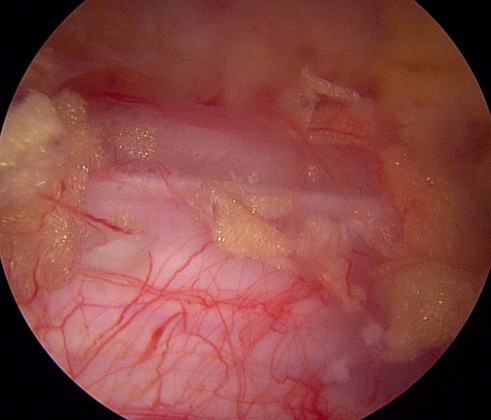

양방향 척추 내시경을 통한 다발성 척추 협착증의 치료 [온종합병원 척추센터 우영하 소장 ]

척추관 협착증은 척추관이 좁아지거나 협착되어 척수나 신경근을 압박하는 상태를 말합니다. 이런 경우, 양방향 척추 내시경이 매우 유용한 치료 수단이 될 수 있습니다.

- 계획: 양방향 척추 내시경은 미세한 카메라와 도구를 사용하여 척수와 주변 신경 구조를 정밀하게 시각화할 수 있습니다. 이를 통해 정확한 진단을 내릴 수 있으며, 각 환자에게 맞는 개별적인 수술 계획을 수립할 수 있습니다.

양방향 척추 내시경은 척추관 협착증과 같은 척추 질환의 치료에 있어서 현대적이고 효과적인 접근법 중 하나로 인정받고 있습니다.